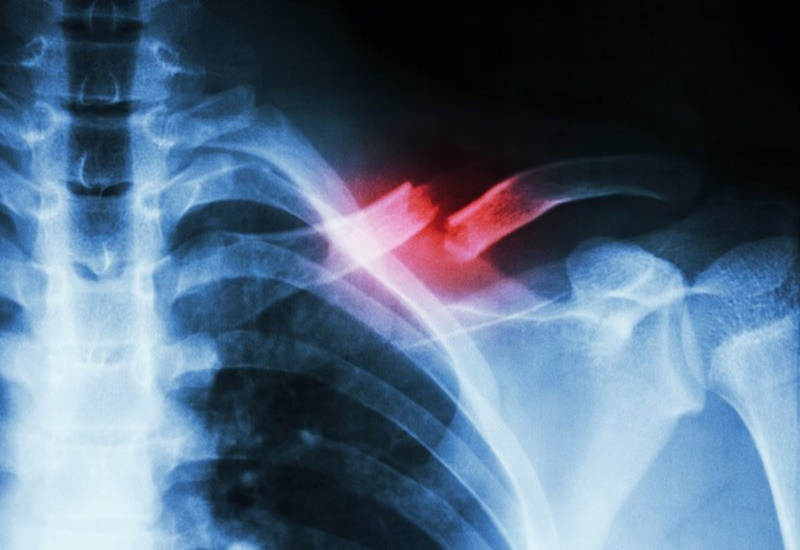

Gãy xương đòn là một chấn thương thường xảy ra tại vùng vai, do va đập trực tiếp hoặc gián tiếp. Câu hỏi gãy xương đòn bao lâu quan hệ được và cách hồi phục nhanh chóng là mối quan tâm của rất nhiều...

Gãy xương đòn là một chấn thương thường xảy ra tại vùng vai, do va đập trực tiếp hoặc gián tiếp. Câu hỏi về việc quan hệ tình dục sau khi bị gãy xương đòn và cách hồi phục nhanh chóng là mối quan tâm...

Sức Khỏe Tình Dục

Gãy xương đòn có quan hệ tình dục được không?